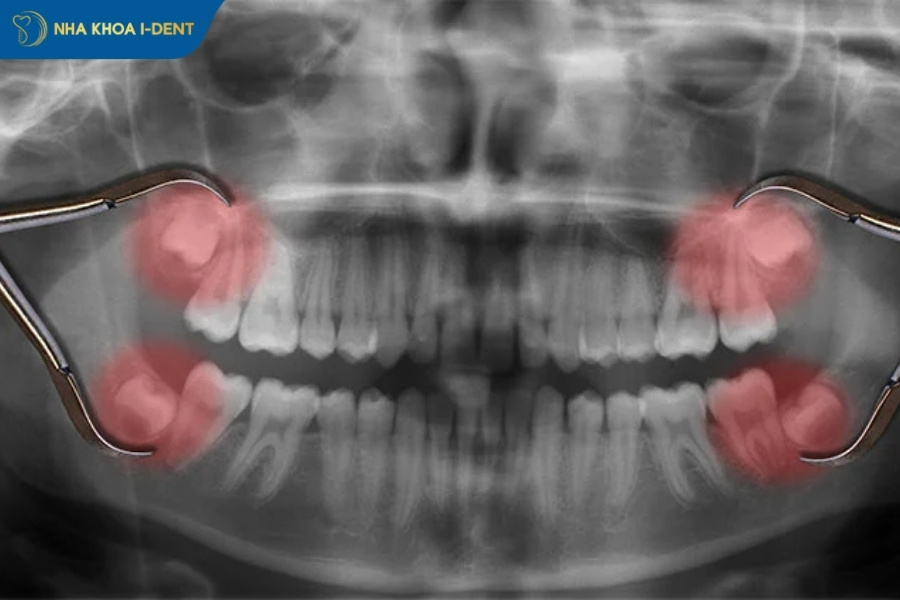

Nhổ răng khôn gây đau và sưng trong khoảng 3-4 ngày đầu và mức độ đau cao nhất trong 1-2 ngày đầu sau khi hết thuốc tê. Tình trạng đau sẽ giảm dần và hết hẳn sau 1 tuần và người có cơ địa tốt thì cơn đau chỉ kéo dài thêm 1-2 ngày. Nhổ răng khôn đau mấy ngày còn phụ thuộc vào độ phức tạp của ca nhổ, vị trí mọc răng khôn và thể trạng mỗi người.

Thứ nhất, quá trình nhổ răng khôn đòi hỏi nha sĩ phải rạch nướu, bóc tách mô mềm bao quanh răng, thậm chí mài xương hàm để tiếp cận rễ răng nằm sâu. Với những trường hợp răng khôn mọc lệch hoặc mọc ngầm hoàn toàn trong xương, bác sĩ buộc phải cắt nhỏ răng thành nhiều mảnh trước khi lấy ra, điều này tạo ra diện tích tổn thương lớn hơn đáng kể so với nhổ răng thông thường.

Nhổ răng khôn thường đau từ 3-7 ngày với các trường hợp đơn giản, tuy nhiên những ca phức tạp có thể kéo dài 10-14 ngày tùy thuộc vào độ phức tạp của ca nhổ, vị trí răng và thể trạng mỗi người.

- Vị trí và hướng mọc của răng khôn: Răng khôn mọc thẳng thường đau 3-5 ngày, răng mọc lệch nhẹ thì dau 5-7 ngày và răng mọc ngầm hoàn toàn, nằm ngang thường đau 7-14 ngày